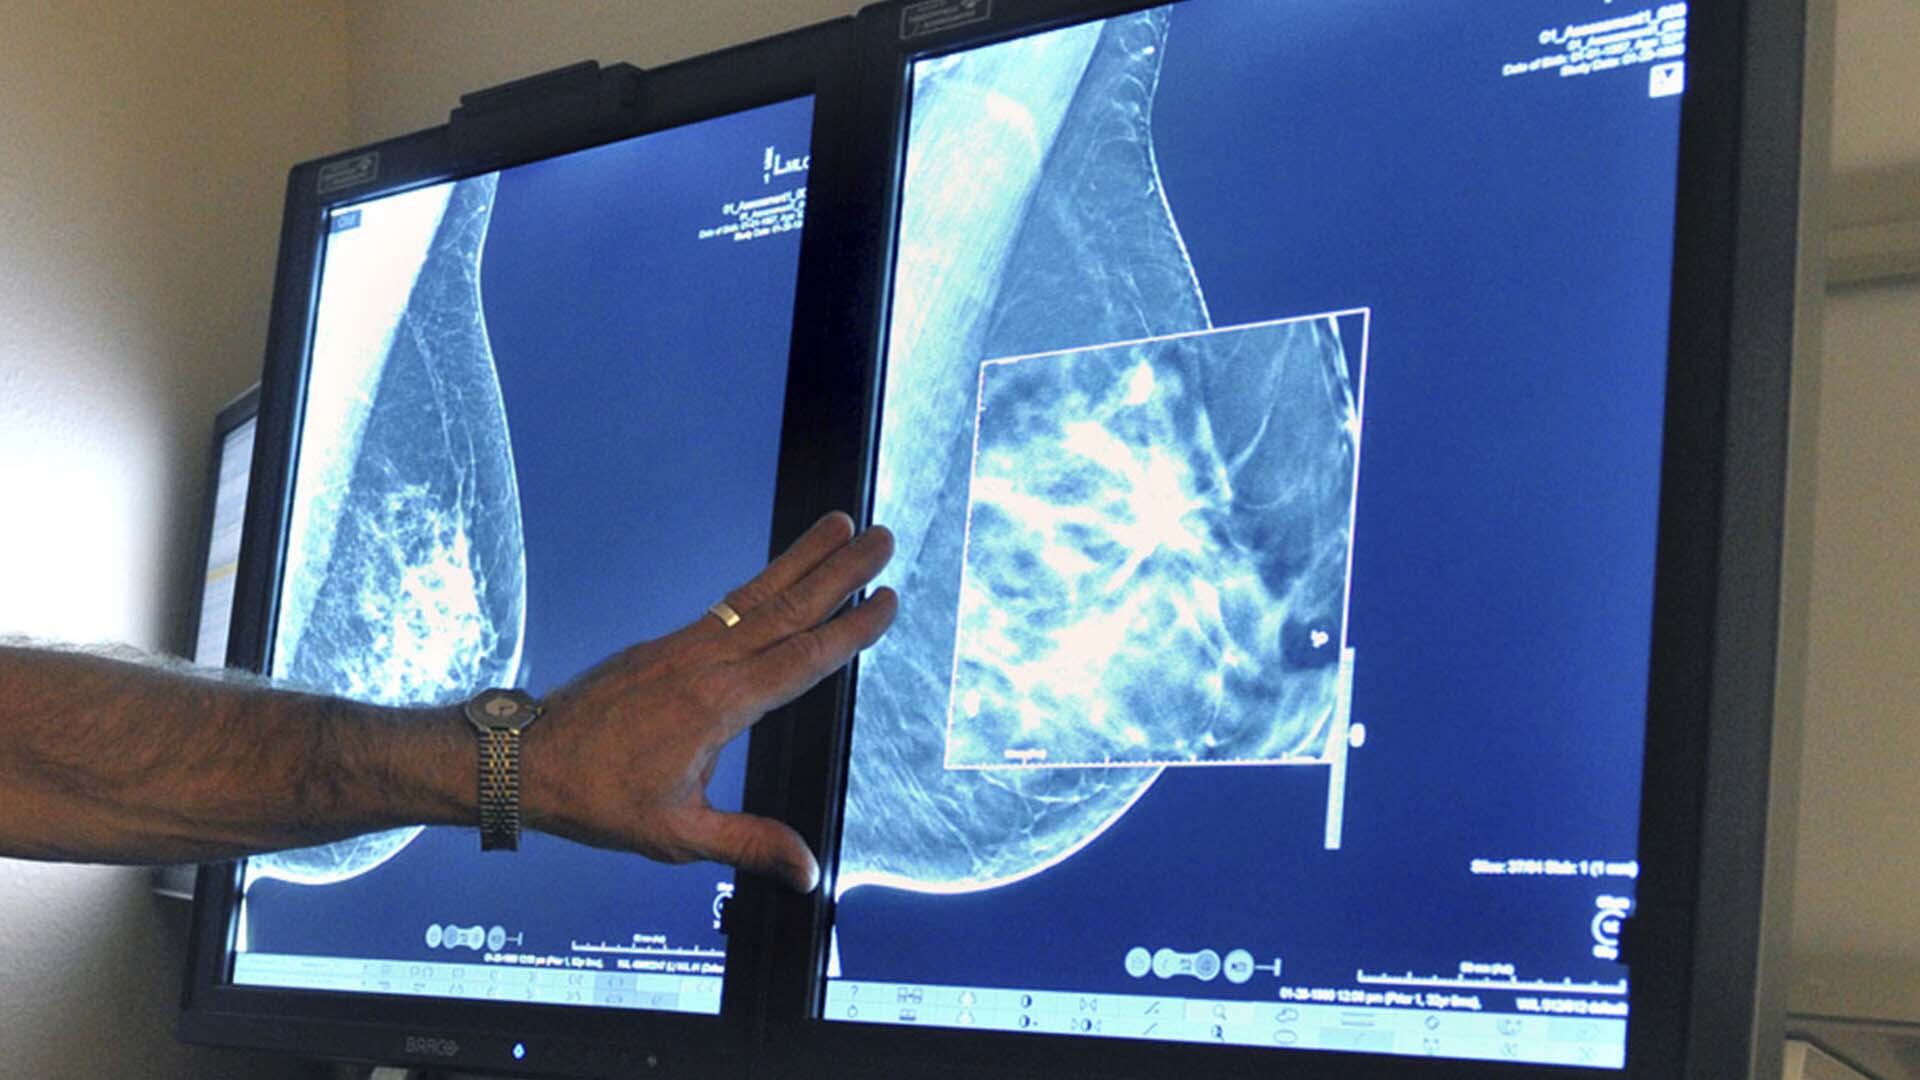

Les femmes de 40 ans et plus auraient avantage à subir une mammographie chaque année pour réduire leur risque d'un diagnostic de cancer du sein plus avancé quelques années plus tard, concluent des chercheuses ontariennes.

La proportion de cancers du sein avancés chez les femmes de 50 à 59 ans est moins élevée dans les provinces où on effectue des mammographies annuelles chez les 40 à 49 ans que dans les provinces qui commencent le dépistage plus tardivement, démontrent leurs travaux.

On constate aussi une plus faible proportion de cancers du sein de stades 2, 3 et 4 chez les femmes de 40 à 49 ans, et de cancers de stades 2 et 3 chez les femmes de 50 à 59 ans, dans les provinces où on procède à un dépistage annuel chez les quadragénaires, explique la nouvelle étude.

En fonction des conclusions de la nouvelle étude, ajoute-t-elle, toutes les femmes de 40 ans et plus devraient subir une mammographie chaque année.